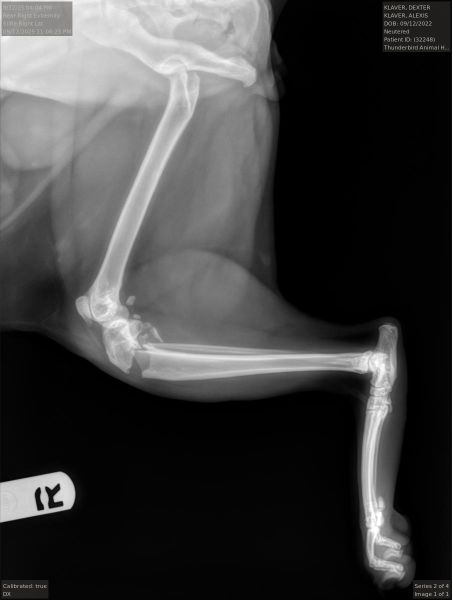

I was hoping to get an opinion whether my cats fractures will heal. He is thought to have been hit by a car and has tibial fractures of both hind legs below the proximal joint. We could not afford the 6000$ surgery to fix them and are splinting instead. I am wondering what the chances are that they will heal? He is eating and drinking, and appears comfortable. Stifle_Left_LatStifle_Right_Lat Thank you

Hello and I'm sorry to read about your kittens problems.   Those radiographs look so uncomfortable!    They are in a very delicate part of the joint and we would recommend that yourself or your vet has an initial chat to an orthopaedic surgeon, specialists in such cases.   Good questions include 'What will be involved in recovery?' And 'What quality of life can I reasonably expect in each case?'